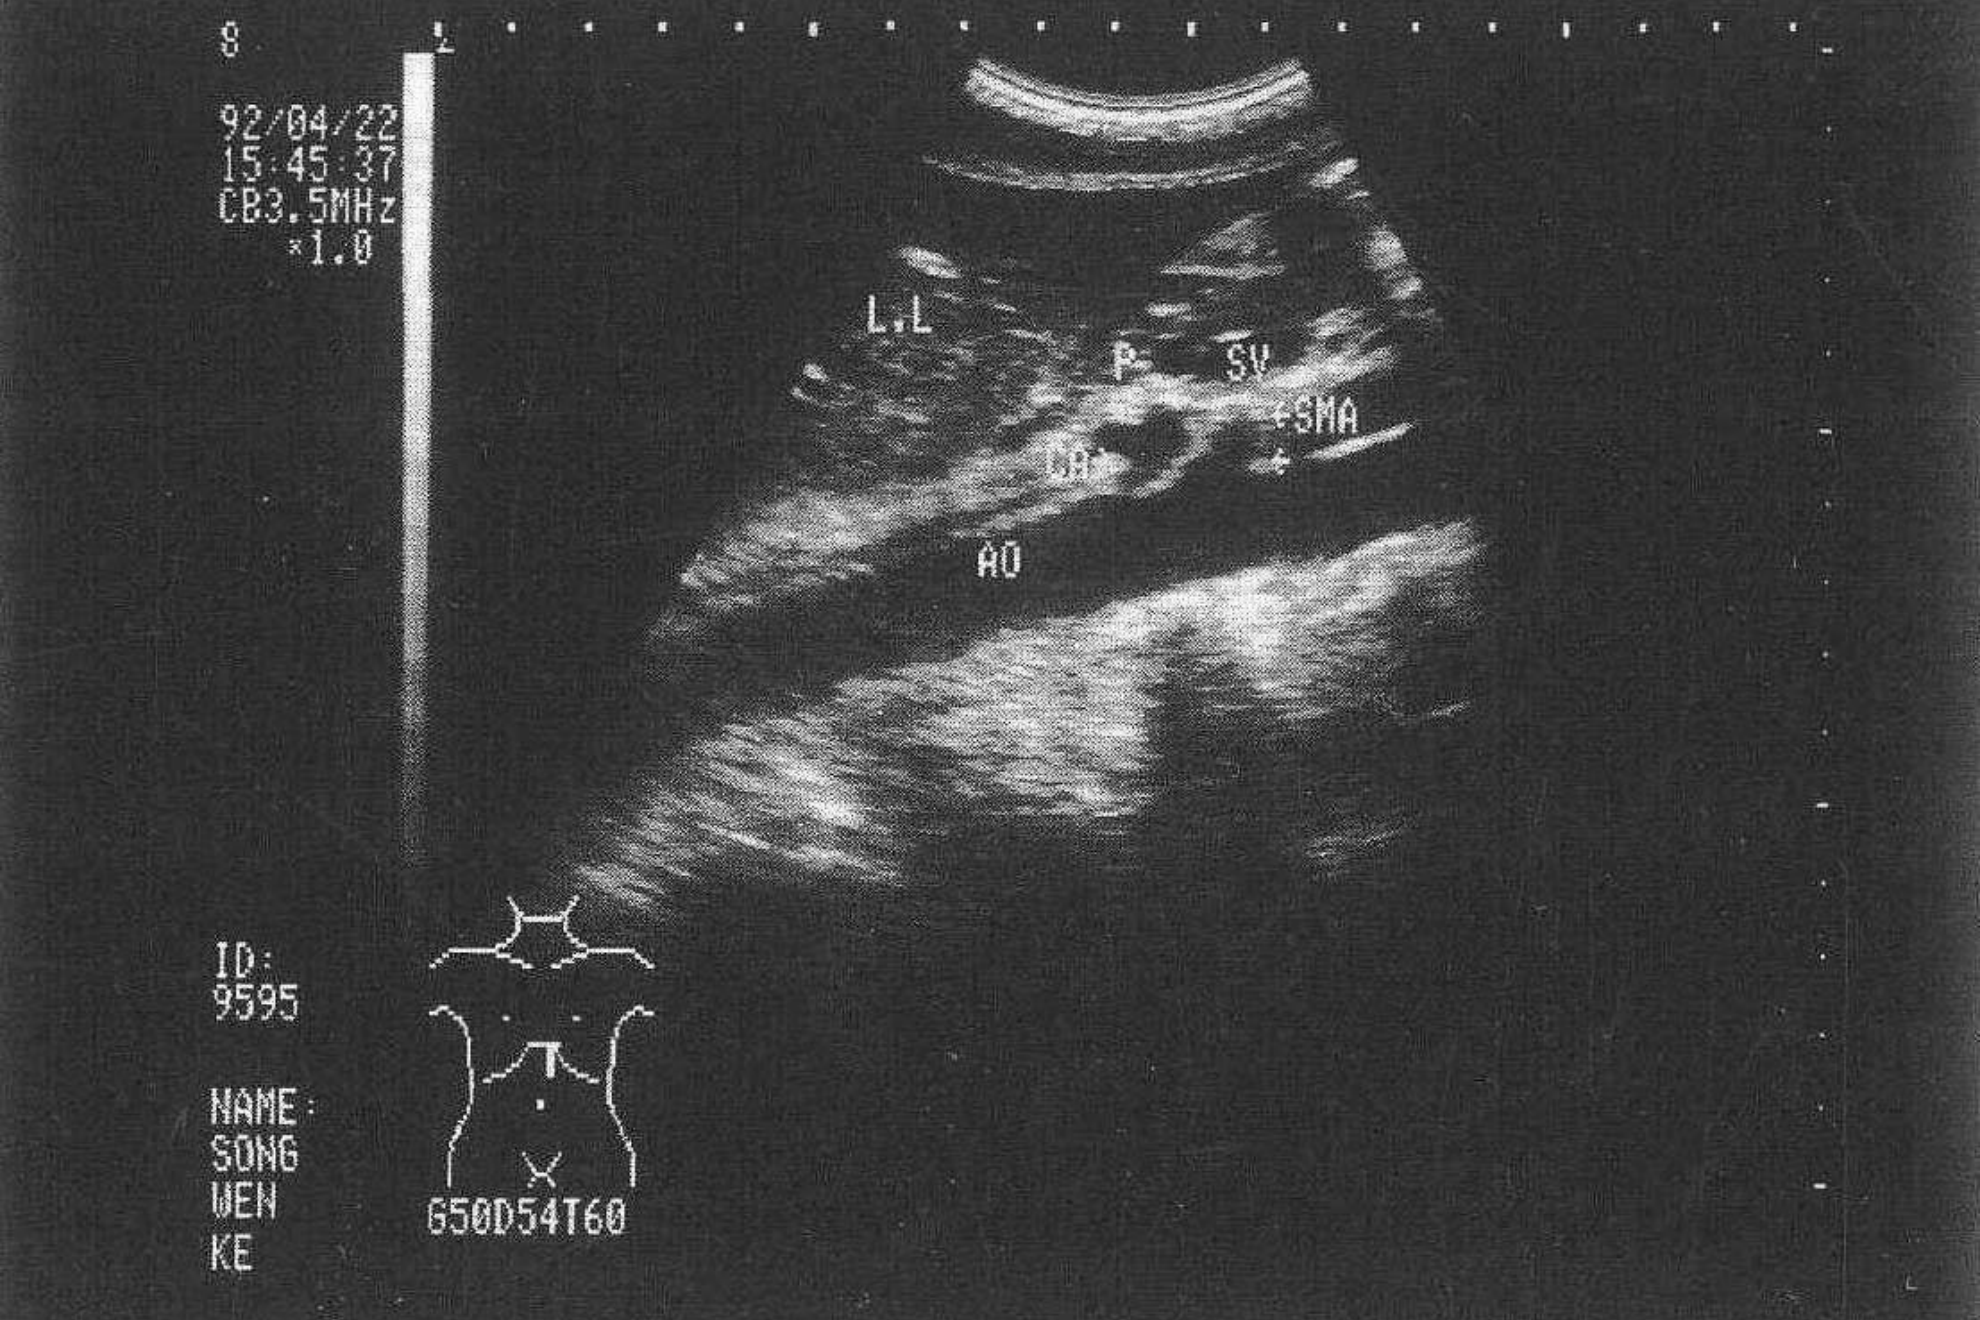

胰腺正常声像图

超声检查时以腹主动脉,下腔静脉,肠系膜上动、静脉和脾静脉等胰周大血管作为识别胰腺的主要标志。胰腺边界光滑而整齐,有时与周围组织间界限不甚清晰。胰头、体、尾前后径的超声测径分别为3cm、2cm及2cm。胰腺实质呈细密的光点回声,多较肝实质回声略强。胰腺中部可见胰主导管通过,其内径一般小于0.2cm。